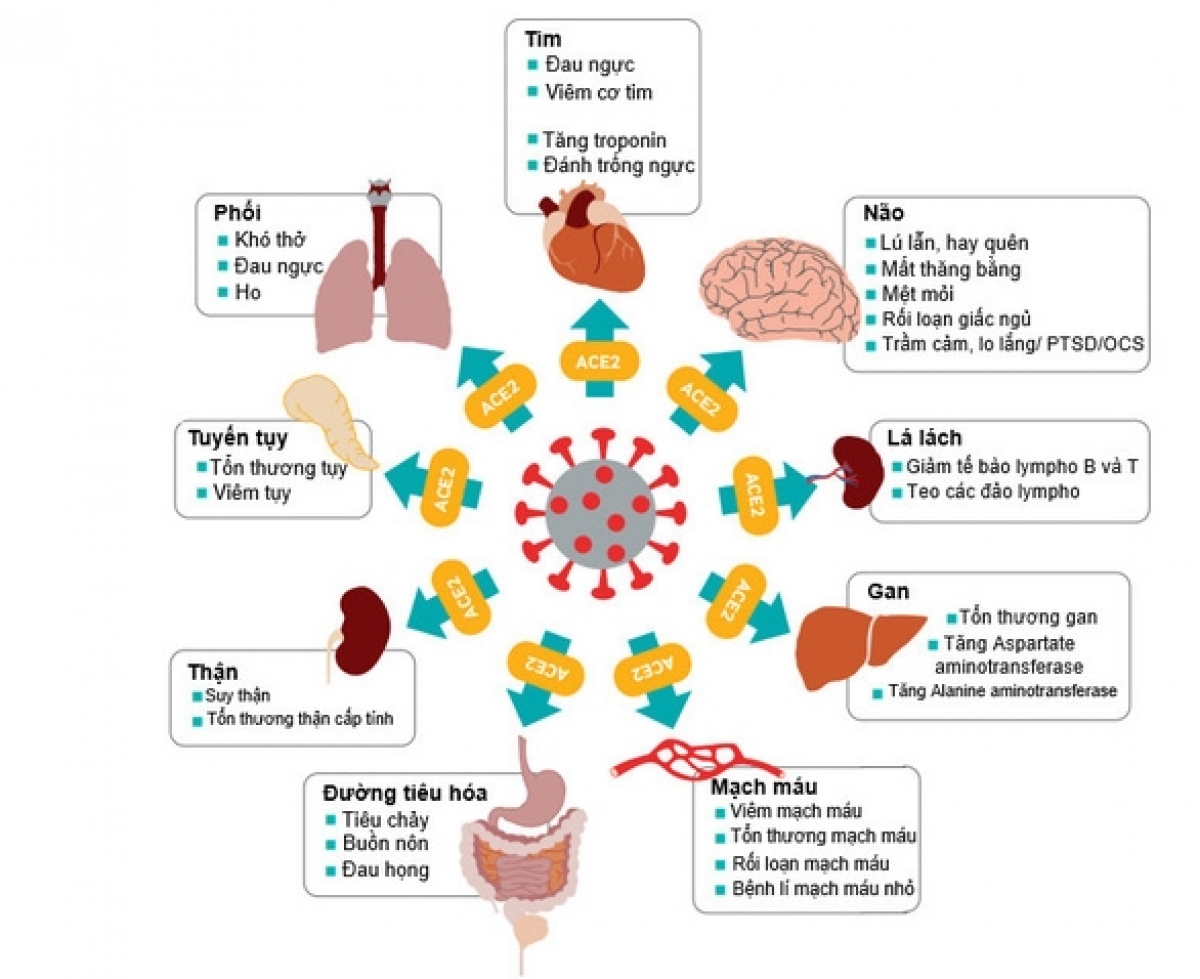

Theo nhiều báo cáo từ châu Á sang châu Âu thì ở giai đoạn nhiễm trùng cấp, có đến 14% bệnh nhân nhiễm COVID-19 bị viêm phổi nặng phải nhập viện, 5% bị hội chứng nguy kịch suy hô hấp cấp tính (ARDS) cần thở máy và điều trị ở đơn vị chăm sóc tích cực. Và ARDS cũng là nguyên nhân chính gây tử vong trong giai đoạn cấp. Những thống kê này cho thấy tổn thương phổi là vấn đề trọng yếu của bệnh COVID-19.

Xơ phổi hậu COVID có thể hiểu nôm na là tình trạng nhu mô phổi bị phá hủy trong giai đoạn cấp tính sẽ không thể phục hồi trạng thái nhu mô phổi bình thường, mà thay bằng những mô xơ (đặc biệt ở bệnh nhân bị viêm phổi nặng và ARDS).

Những tổ chức xơ này không thực hiện được chức năng trao đổi khí CO2 và O2 ở phổi, dẫn đến tình trạng khó thở, đặc biệt là khó thở khi vận động thể lực.